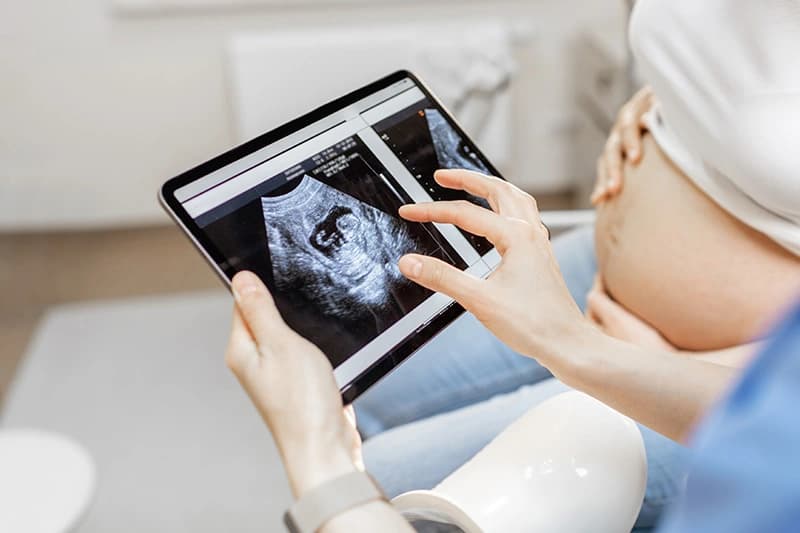

An Early Pregnancy Ultrasound is a scan performed shortly after finding out you are pregnant. Usually, 6 to 10 weeks after conception and the purpose of the scan is to confirm the pregnancy, assess early viability and provide an approximate date of the pregnancy.

An early pregnancy scan is usually performed shortly after finding out you are pregnant.

This is usually 6 to 10 weeks after conception and the purpose of the scan is to confirm the pregnancy, assess early viability and to provide an accurate date of the pregnancy (the scan is often referred to as viability or dating scan).

The scan is performed with the ultrasound placed gently over the abdomen with gel to allow the sound waves to travel through the skin.

When you schedule your pregnancy scan, rest easy knowing ultrasound is safe for both you and your baby when performed by a qualified and experienced consultant. Unlike X-rays and other imaging technologies, ultrasounds use soundwaves that have no radiation to capture images of your baby and the inside of your body.

Ultrasound has been used widely for over three decades, and researchers and healthcare professionals have not found any associated risks.

We can provide scan images directly to your smartphone, often on the same day following your appointment. Gain the peace of mind and insight you need, without delay.